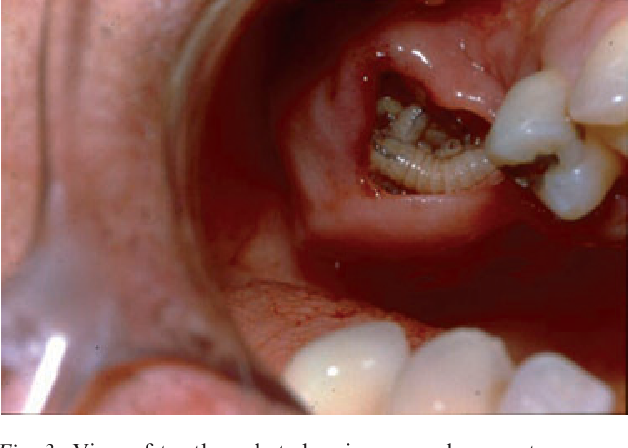

Screwworm infection, for those fortunate enough to be unfamiliar, is as delightful as it sounds. Caused by the larvae of a particularly adventurous fly, it manifests as painful skin lesions oozing with the kind of fluid that would make even the most seasoned medical professional pause. The treatment? Surgical removal of the larvae, followed by the kind of local care that makes you appreciate the mundane joys of being larva-free.